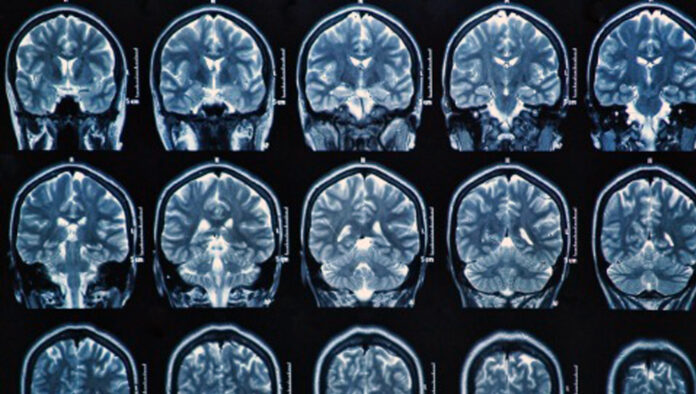

Le metastasi cerebrali sono di fatto il più comune dei tumori cerebrali e fino ad 1/3 dei pazienti che hanno un tumore in altra sede soprattutto se presente al polmone, mammella, rene, colon o cute possono presentare una o più metastasi al cervello. Gli eventuali segni clinici o sintomi come forte cefalea, comparsa di deficit motori, confusione spazio-temporale, crisi epilettiche devono essere interpretati come un potenziale danno cerebrale e, soprattutto se presenti in pazienti con neoplasie primitive note, essere interpretati come possibili manifestazioni di lesione/i secondarie.

Sì, ed è fondamentale essere in grado di riconoscerli. Si tratta di cefalea, deficit di forza focale (incapacità di muovere un arto), deficit cognitivi (disturbi di memoria e spazio temporale) e crisi epilettiche. Questi segni e sintomi sono di fatto comuni anche ad altre lesioni neoplastiche cerebrali ma ciò che è importante e la tempestività della diagnosi. Non di rado accade che dall’individuazione di una metastasi cerebrale si riesce poi a risalire al tumore primitivo.